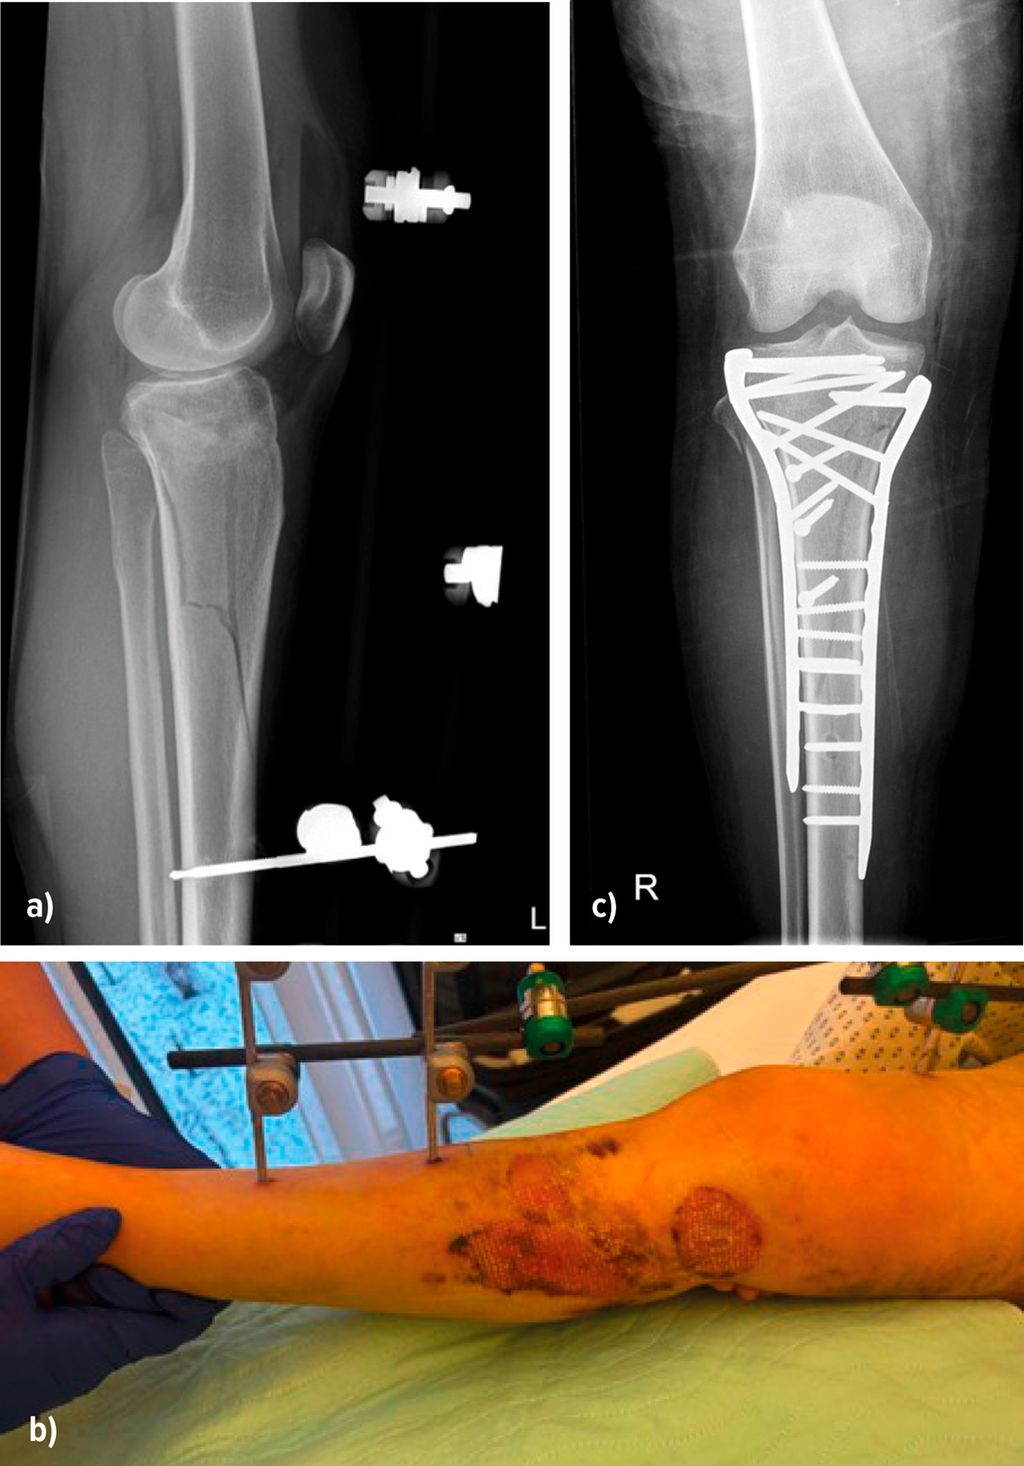

Bei stark geschwollenen Weichteilen ist ein zweizeitiges Vorgehen mit primärer Anlage eines gelenkübergreifenden Fixateur externe für 5–10 Tage erforderlich, um die Weichteile zur Ruhe kommen zu lassen und das Risiko für Wundheilungsstörungen zu senken (Abb.4).

Abb. 4: Anlage eines Fixateur externe bei Weichteilkomplikation und anschließende Versorgung mit einer Platte